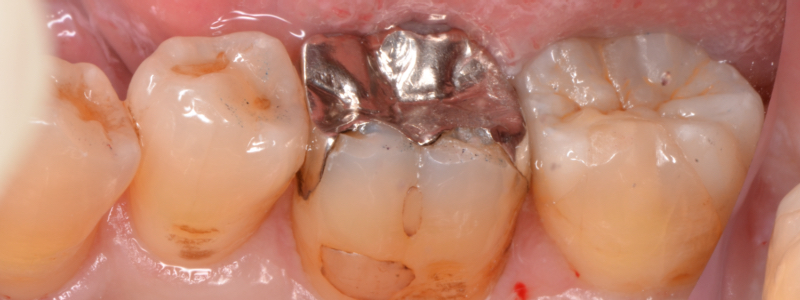

奥歯に銀歯が入っています。

銀歯と歯の境目には、

- 左◯:歯が欠けた結果できた隙間

- 右○:咬み合わせの歯と強く当たって細かく欠けた跡

があります。

患者様は、「舌で触るとザラザラする」という感覚だと思います。